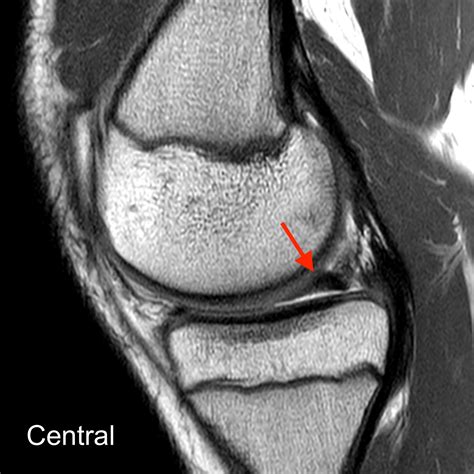

To grasp the severity of this injury, it helps to visualize the knee joint. Your meniscus is a wedge-shaped piece of fibrocartilage that sits between your thigh bone (femur) and your shin bone (tibia). It distributes weight and stabilizes the joint. When a bucket handle meniscus tear occurs, the inner portion of the cartilage detaches from the main body but remains attached at the front and back. This loose piece can then displace, or “flip,” into the center of the joint, physically blocking the knee from moving normally.

2. Imaging Tests: While X-rays are useful to rule out bone fractures, they cannot visualize the meniscus. An MRI (Magnetic Resonance Imaging) scan is the gold standard for diagnosing a bucket handle meniscus tear, as it provides detailed images of the soft tissue cartilage.